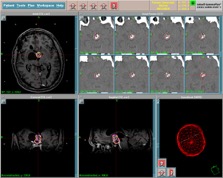

l’imagerie

il s’agit d’un tumeur supra-sellaire souvent calcifiée et kystique

l’imagerie étudie ses rapports avec l’hypothalamus, les voies visuelles, les structures du sinus caverneux.